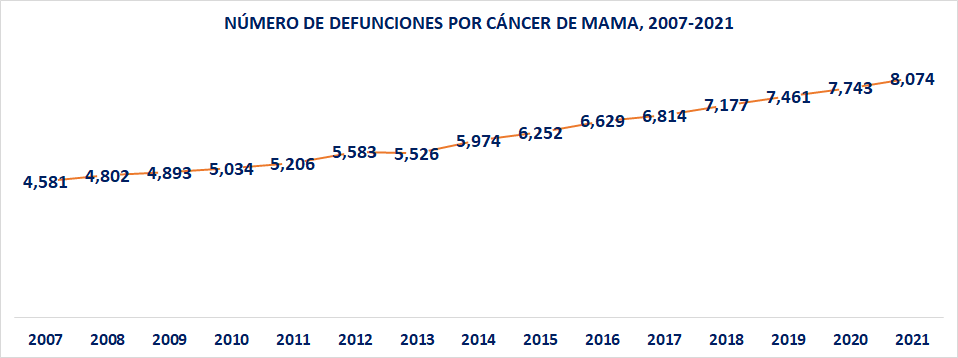

Empeoran los indicadores sobre cáncer de mama

A diferencia del cáncer de cérvix, causa por la cual se ha logrado, hasta ahora una reducción en la tasa de mortalidad; aunque un número casi constante en el número absoluto de decesos anuales; en el caso del cáncer de mama México ha experimentado un muy importante incremento en el número absoluto de casos de defunción, pero también en la tasa anual.

En efecto, mientras que en el año 2007 el número de defunciones por cáncer de mama, acaecidos en el país, fue de 4,581; para el año 2012 se incrementó a 5,583; en el 2018 llegó a 7,177; mientras que el número proyectado para este 2021 es de 8,074.